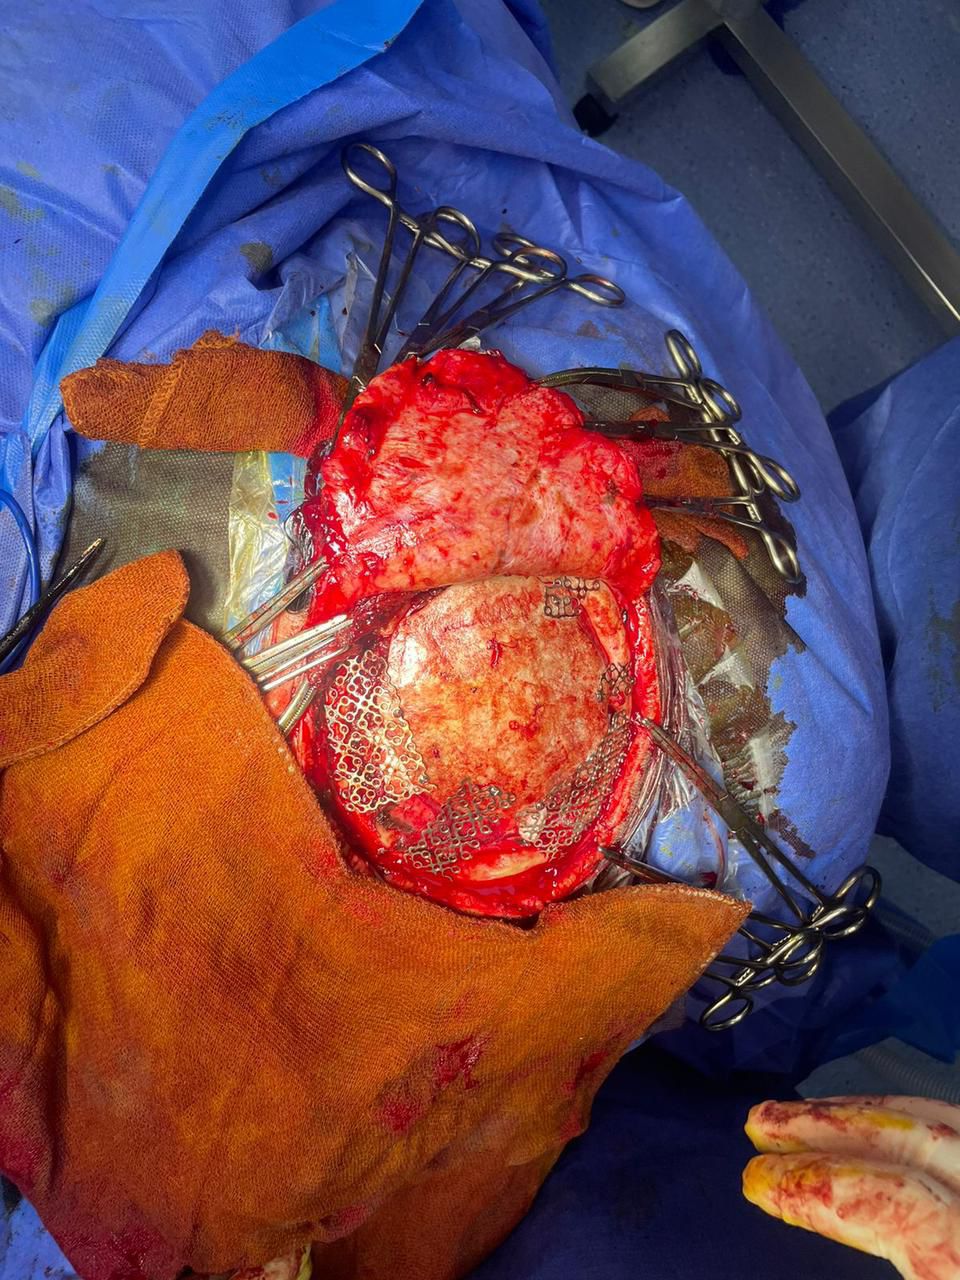

وبعد استقرار الحالة، تقرر إعادة زرع عظام الجمجمة من التجويف البطني إلى موضعها الأصلي، لكن نتيجة لاحتمالية حدوث ضمور بالعظام المزروعة، تم تجهيز شبكة من التيتانيوم ثلاثية الأبعاد لترقيع الجمجمة بالشكل المناسب.

وقد أُجريت الجراحة بواسطة فريق متخصص بقسم جراحة المخ والأعصاب بقيادة والدكتور علي موافي استشاري جراحة المخ والأعصاب، وبإشراف الدكتور أحمد بدران مدير مستشفيّ السنبلاوين العام .

وتمت العملية بنجاح، عبر فتح الجمجمة بطريقة تجميلية تراعي الحفاظ على نمو الشعر، مع تثبيت شبكة التيتانيوم لإعادة الشكل الطبيعي للرأس.